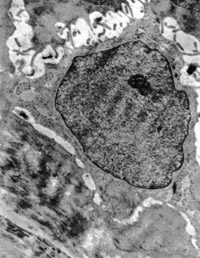

5-2-2 傷后第1天,毛細(xì)血管內(nèi)皮細(xì)胞核固縮,管腔內(nèi)血液凝集和瘀滯  TEM×6000